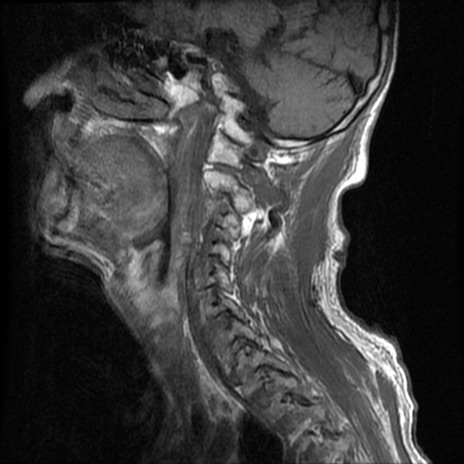

症例46 頚椎MRI T1WI(矢状断像)

頚椎MRI

T2WI(矢状断像)